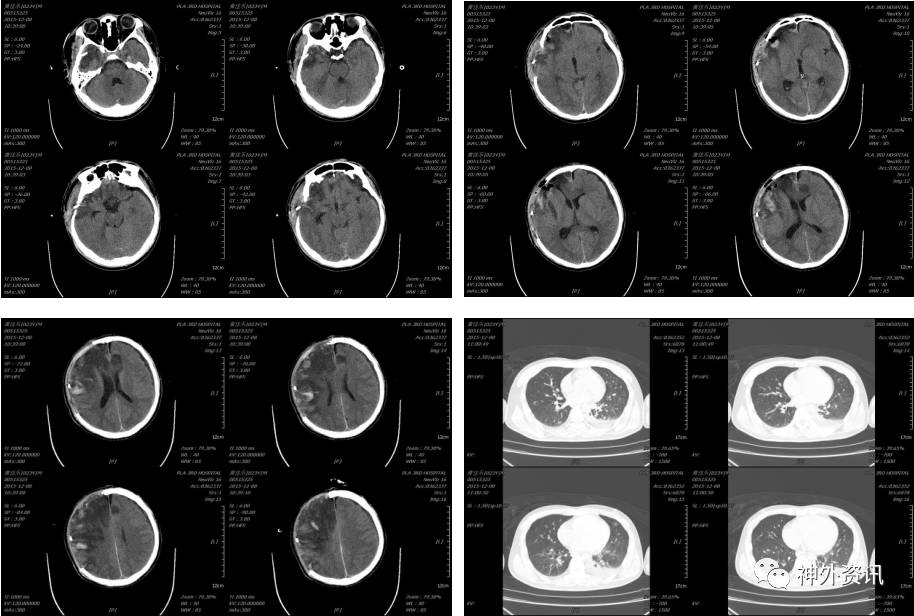

2015-12-02 12:33 伤后1小时我院急诊科复查头颅CT(2015-12-02 12:33):

入科后急诊在全麻下行去骨瓣减压及硬膜下血肿清除术,植入脑实质内颅内压监测,术后患者颅内压正常范围,生命体征平稳,术后第二日复查头颅CT及胸部CT(术后约14小时,2015-12-03 09:33):

患者术后虽然颅内显示正常,但挫伤出血量大,脑肿胀明显,行二次开颅颅内血肿清除术,术后复查头颅示(2015-12-04 09:05):

术后给予镇痛、镇静、机械通气、脱水、止血、抗感染、目标性体温控制、营养支持等治疗,术后4天复查头颅CT及胸部CT示(2016-12-08 10:39):